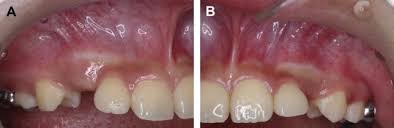

Window technique this represents the simplest form of open exposure. The open exposure technique consists of surgical removal of the tissue covering the tooth, leaving it exposed to the oral cavity. 26,27 in the case shown here, closed eruption was chosen for the impacted central and. Within the different approaches there exist two main options for the subsequent eruption of the impacted teeth (6): Open eruption technique the open eruption technique was the first method used to uncover impacted teeth.

Chaushu s(1), becker a, zeltser r, vasker n, chaushu g. Preorthodontic exposure and autonomous eruption The open exposure technique consists of surgical removal of the tissue covering the tooth, leaving it exposed to the oral cavity. Given the reported success of forced eruption, the technique requires… continue reading The present study provides information to patients and clinicians. Duration of surgical procedure (in min) click here to view Dr vanarsdall recommends open exposure with a repositioned gingival flap (pediculated connective tissue graft) above the impacted canine. Apically position flap the goal is to choose a technique that exposes the canine within the a zone of keratinized mucosa without involvement of the cementoenamel junction 27. The open eruption technique may be performed in two different ways, as described below. If the canine crown is positioned distal to the mesial aspect of the lateral incisor, an open technique is performed. Forced eruption can preserve the natural root system and related periodontal architecture, resulting in years of additional service for the patient. Open eruption through a window; In this technique sufficient space.

If the canine crown is positioned distal to the mesial aspect of the lateral incisor, an open technique is performed open'er. (1) window technique, (2) full flap open procedure, and (3) apically repositioned flap technique.

Interventions for promoting the eruption of palatally displaced permanent. If the crown is positioned mesial to the lateral incisor, a closed technique for the pataltal eruption of canine. Dr kokich recommends open and preorthodontic exposure of palatally impacted canines. Despite the unconcealed allocation, the outcome duration of canine's eruption is probably in low risk of bias as the protocol of open and closed technique is mentioned clearly, any possible confounders (age, depth of impaction) have similar distribution at baseline among groups and the definition of eruption is objective. (1) window technique, (2) full flap open procedure, and (3) apically repositioned flap technique.